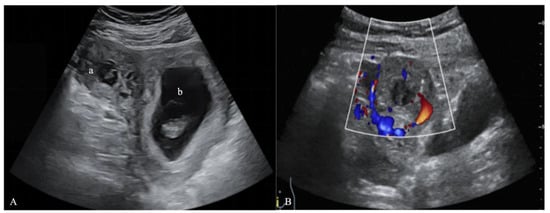

A 31-year-old woman came to Peking University Shenzhen Hospital complaining of slight vaginal bleeding and tenesmus for 8 h. She had undergone in vitro fertilization (IVF) and transferred two frozen embryos into the uterine cavity at the hospital 38 days prior. On the 14th day after embryo transfer (ET), she routinely received a serum β-human chorionic gonadotropin (β-hCG) test, which showed 2372 IU/L, indicating pregnancy. On day 30 after ET, the patient had her first ultrasound, which revealed an embryo in the uterus. During this period, the patient and the embryo were in a stable condition. However, on the 38th day after ET, she had a small amount of vaginal bleeding and tenesmus, so she returned to the hospital for treatment. Two gestational sacs were unexpectedly discovered by transvaginal ultrasonography (TVUS) on day 38 after ET: one was in the uterine cavity with a fetal bud of 15 mm long and with a fetal heartbeat, and the other was located in the right interstitial part of the fallopian tube, which was not communicated with the uterine cavity. In this gestational sac mass, there was a fetal bud about 5 mm long, and the fetal heart rate was not yet obvious, but the blood flow signal around the mass was abundant (Figure 1). In addition, the patient’s serum β-hCG level was shown to be higher than 264,000 IU/L. She was finally diagnosed with HIP based on TVUS, serum β-hCG levels, and multidisciplinary expert consultation.

Figure 1.

Ultrasound images on the 38th day after ET. (A) A two-dimensional ultrasound image: (a) the interstitial gestational sac in the interstitium of the right fallopian tube and (b) the intrauterine gestational sac. (B) A color Doppler ultrasound image showing an abundant blood flow signal around the IP.